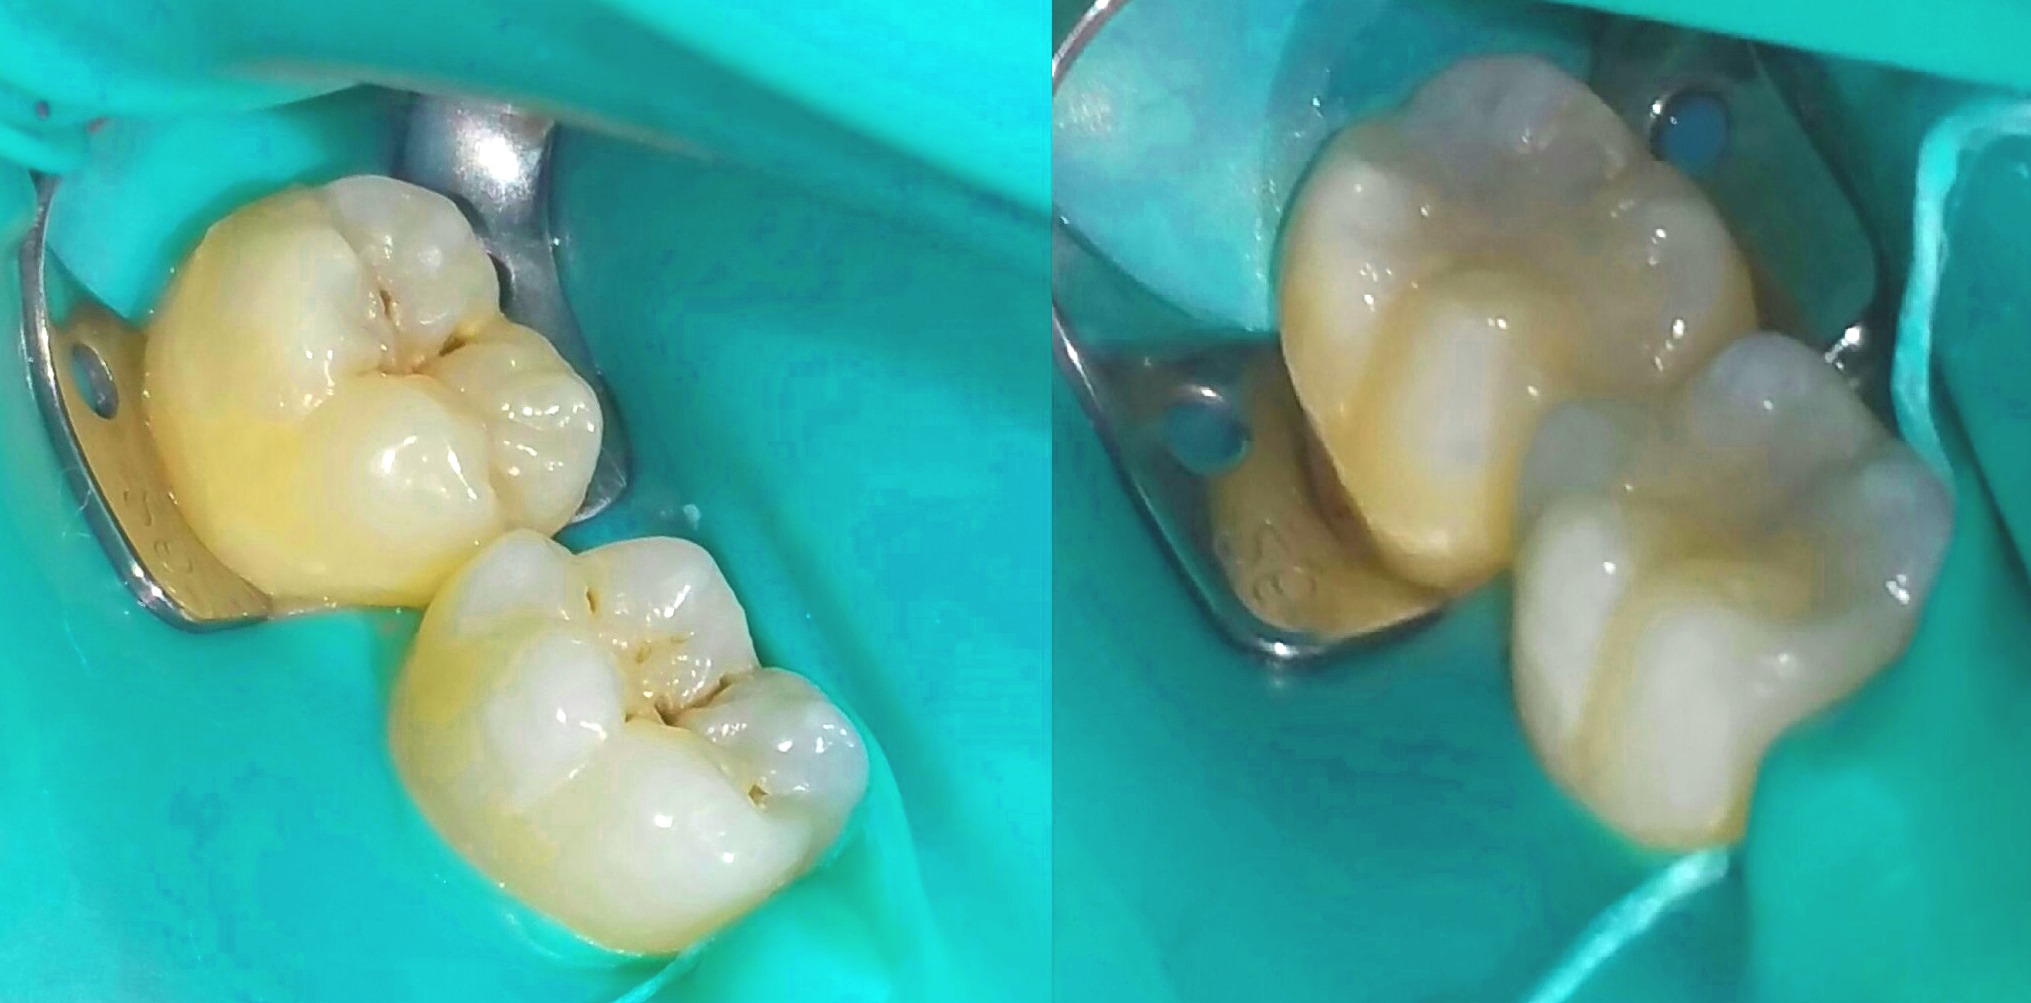

| 복합 레진 충전 | 복합 레진을 얇게 층층이 쌓아 올리면서 광중합하여 수축을 최소화하고, 치아 형태를 재현함 |